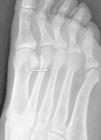

Non-traumatic metatarsal fracture: Uncommon complication of primary antiphospholipid syndrome

Fractura metatarsiana no traumática: Una complicación rara del síndrome antifosfolípido primario